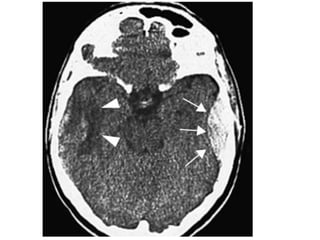

Head CT

“Blood Can Be Very Bad”

61

Blood Can Be Very Bad

• Blood

• Cisterns

• Brain

• Ventricles

• Bone

62

63

64

65

66